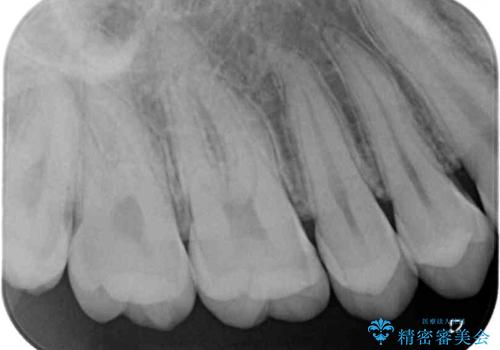

フロスが引っかかる セラミックインレーによるむし歯治療

- ウェブサイトの症例(https://seimitsushinbi.jp/case/9473/)を見て、同じようにフロスが引っかかるとのことで来院された患者様です。

虫歯を除去した後、セラミックインレーにて修復治療を行うこととしました。

セラミックインレー装着後はフロスの引っかかるストレスから解放され、患者様には大変満足していただきました。